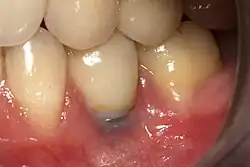

The area of the mouth that is missing a tooth is identified.

An area with a single missing tooth